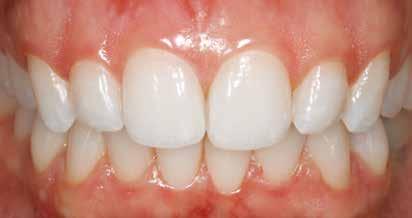

A fogászati kezelések során manapság már nem kizárólag az esztétikai megjelenés helyreállítására törekszünk. Sokszor a kedvezőtlen esztétikai megjelenés hátterében álló okok következményes módon a fogazat funkcionális működését is károsítják, így a kezelések során ezeknek a helyreállításával is foglalkoznunk kell. A különböző funkcionális és esztétikai diszkrepanciák kezelésére számtalan módszer létezik, ám ezen fogászati beavatkozások mindegyikében közös, hogy a kivitelezésük során nagyon szoros együttműködésre van szükség a kezelést végző fogorvos és a munkáját segítő fogtechnikus között. Az alábbi esetbemutatás során egy fiatal hölgypáciens fogazatának héjak alkalmazásával történő esztétikai és funkcionális rehabilitációját szeretnénk ismertetni.

A 19 éves hölgypáciens azzal a kéréssel jelentkezett a rendelőnkbe, hogy szebb fogakat szeretne. Az első konzultáció alkalmával megkérdeztük, hogy mi zavarja leginkább a fogazatának jelenlegi megjelenésében, valamint azt is megbeszéltük vele, hogy milyen végeredmény elérése esetén lenne maradéktalanul elégedett. Ebben az esetben a kezelési célokat az alábbiakban határoztuk meg:

A páciens fogazata esztétikai megjelenésének és funkcionális működésének a lehető legtöbb, saját foganyag megtartása mellett történő helyreállítása (1. és 3. ábra).

A kezelés során az jelentette a legnagyobb kihívást, hogy a héjakkal ellátott fogak élethűen utánozzák a természetes fogazat megjelenését. A fogpótlás színének, valamint a restaurátumok felszíni textúrájának és alakjának harmonikusan kell a páciens arcesztétikájához és karakteréhez illeszkednie.

A tényleges protetikai ellátás megkezdése előtt a páciens mosolygás közben látható fogait otthoni fogfehérítés keretei között a kérésének megfelelő A1-es fogszín eléréséig fehérítettük. A fehérítés során a későbbiekben héjakkal ellátásra kerülő fogak színén nem változtattunk. A fogak előkészítése részeként csupán a két felső nagymetsző (1.1,2.1) incizális élét kellett kismértékben redukálni. A többi felső front fog (1.3,1.2,2.2,2.3) nem került preparálásra.

nak megfelelően – előkészítjük (orthofoszforsavval történő savazás, lemosás, szárítás és bond réteggel történő fedés). Ezzel egyidejűleg a ragasztásra kerülő héjak is előkészítésre kerülnek (hidrofolysavval történő savazás, lemosás, szárítás, szilanizálás, bond réteggel történő fedés, és végül az alkalmazni kívánt ragasztóanyag felvitele). Ezután a héjakat a fogak felszínén egyesével pozicionáljuk, majd néhány másodpercen keresztül polimerizációs lámpa segítségével megvilágítjuk. Ezt követően a kifolyó ragasztófelesleget eltávolítjuk, majd elvégezzük a restaurátumok végső polimerizálását. A héjak végleges rögzítését követően az esetlegesen visszamaradt ragasztómaradványok eltávolításra kerülnek, valamint ellenőrizzük az okklúzió és artikuláció közben létrejövő fogérintkezéseket. Az optimális esztétikai eredmény biztosítása érdekében kiemelt jelentősége van a papillák helyreállításának (rózsaszín esztétika). A modern fogorvoslás egyik kiemelt célja a fehér- és rózsaszín esztétika közti harmonikus egyensúly megteremtése. A papillák színe, nagysága és szimmetrikus megjelenése meghatározó szerepet tölt be a rózsaszín esztétika kialakításában. Az íny lefutása ugyancsak rendkívül jelentős mértékben befolyásolja a páciens fogazatának esztétikus megjelenését.

A cikkünkben bemutatásra kerülő eset ellátása során preparációt nem igénylő héjak készítése mellett döntöttünk. A héjak készre vitele során a platinafólia technikát alkalmaztuk. Annak ellenére, hogy az elkészítésre kerülő héjak rendkívül vékonyak, és ezáltal a végleges rögzítésük előtt jelentős törésveszéllyel állunk szemben, összességében mégis olyan minimál invazív kezelési eljárásnak számítanak, amely segítségével kifogástalan esztétikai eredményeket lehet elérni. A fent leírtak alapján bátran javasoljuk e módszer alkalmazását.